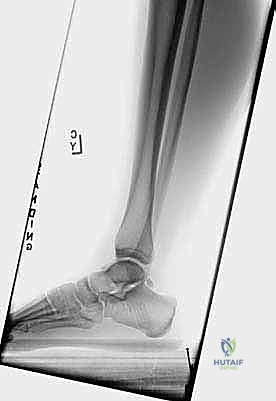

- الأشعة السينية (X-rays): لالتقاط صور دقيقة تظهر وجود العظمة المثلثية (Os Trigonum) أو كسر في بروز ستيدا.

- التصوير بالرنين المغناطيسي (MRI): وهو الفحص الذهبي الذي يعتمد عليه الدكتور هطيف لرؤية الأنسجة الرخوة، وتحديد مدى الالتهاب، وتورم العظام، وحالة الأوتار المحيطة، وتأكيد وجود الانحشار بدقة متناهية.